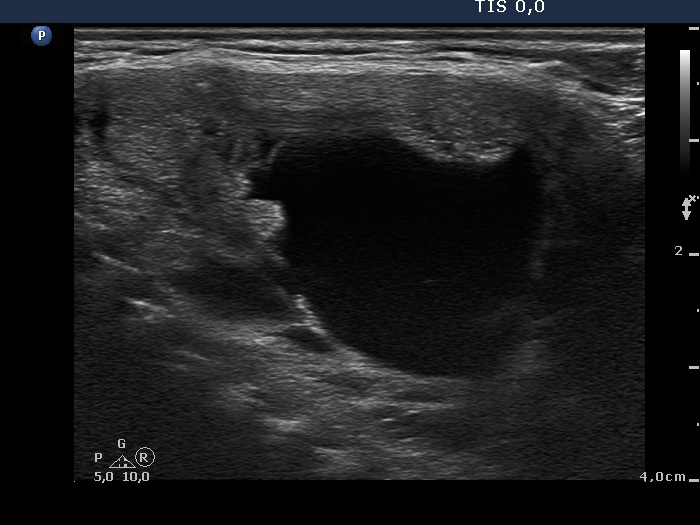

Intranodular hyperechogenic figures - case 608 (ultrasonographic picture 6)

Isthmus, another longitudinal view.